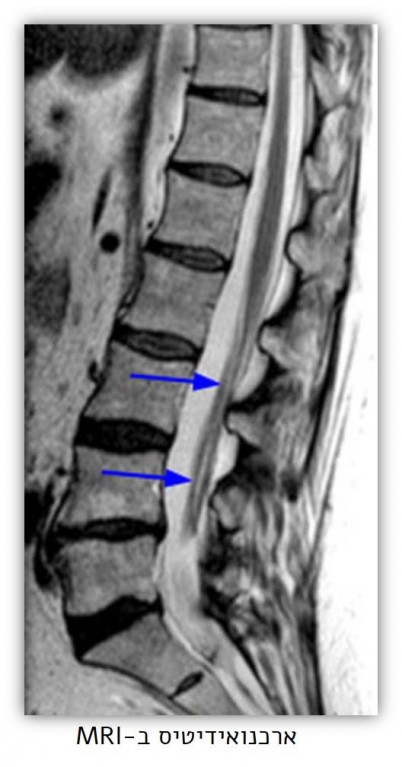

ארכנואידיטיס או ארכנואידיטיס הידבקות - Adhesive Arachnoiditis היא מחלת כאב כרונית, הנגרמת בשל דלקת של קרומי מערכת העצבים המרכזית, או ליתר דיוק "הקרום העכבישי" או Arachnoid membrane. כבכל מחלה, ככל שהארכנואידיטיס תתגלה מוקדם יותר ותטופל בסמוך ככל האפשר לזמן הארעותה, כך גדלים הסכויים שחומרתה תפחת והיא תטופל ביעילות גבוהה יותר.